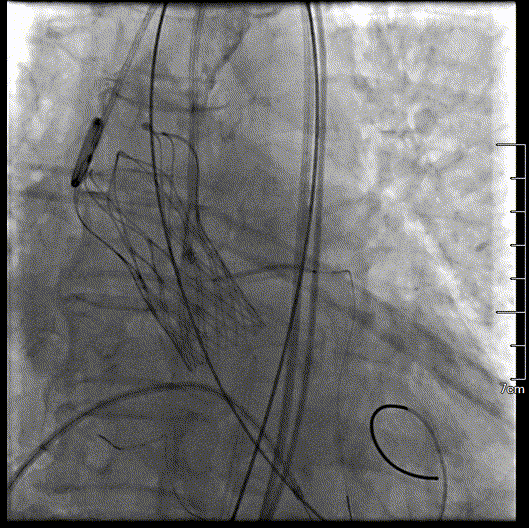

主动脉根部造影

球囊预扩,确认冠脉风险

瓣膜初始定位

瓣膜释放到可回收临界点

临界点处造影

瓣膜完全释放过程

瓣膜完全释放形态良好

工作钢丝送入左室进行起搏,180bpm起搏下预扩张主动脉瓣,完全扩张后,主动脉根部造影无反流,回撤球囊停止临时起搏。